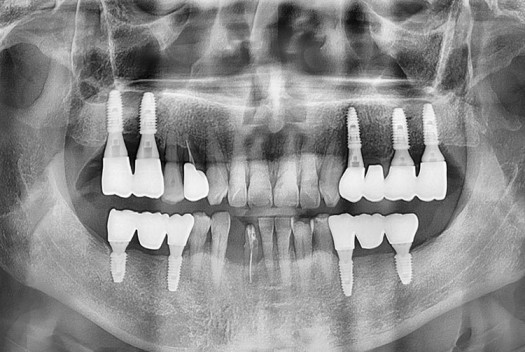

치료후 : 2025-05-22

PX20250522_113417_9796_51218347.jpg

세종치과는 많은 환자와 다양한 케이스를 바탕으로 항상 편안한 임플란트 수술을 제공하고자 노력하고,

오래동안 튼튼히 쓸 수 있는 임플란트 수술을 가장 큰 목표로 삼고 있습니다.